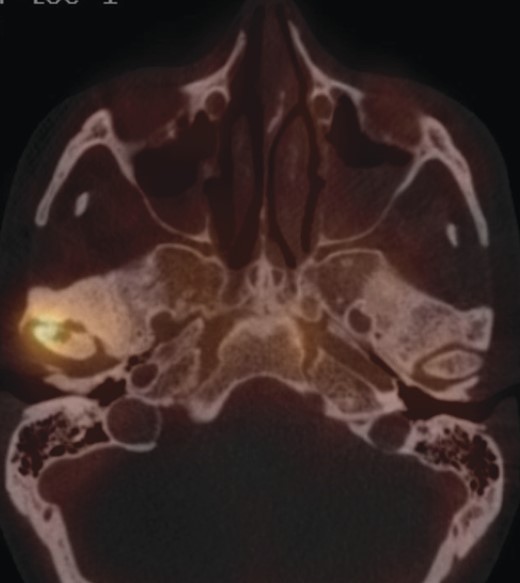

A full-body skeletal scintigraphy was done, which did not show an obvious pathology in the right TMJ (Fig. 3). Due to this, a SPECT/CT was performed for clarification. High uptake of nuclides was seen around the osteolysis of the right condyle (Fig. 4). Sclerotic changes without increased uptake were noted in the left condyle (Fig. 5).

The sclerosis of the left TMJ was suspected to be a non-active metastasis.

In summary, from the radiological findings bilateral TMJ metastases were diagnosed, which were, however, not confirmed histologically.